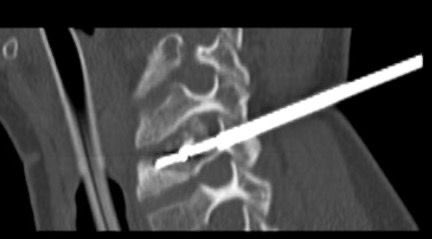

Thread/ Very excited to see our RESCUE-II study in print JACC Journals Advances. In this study we evaluated bolus-only r-tPA w/o infusion for management of acute intermediate-risk PE. #CardioTwitter #ACCFIT sciencedirect.com/science/articl…